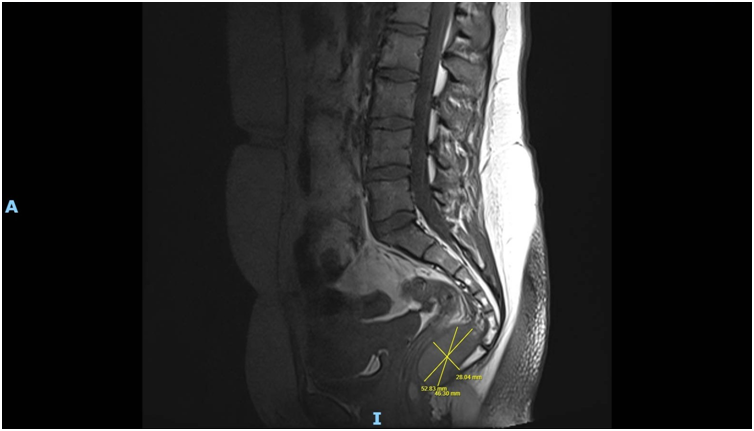

Imaging via MRI and CT demonstrated a complex, encapsulated lesion with peripheral enhancement and restricted diffusion. Multidisciplinary evaluation suggested a congenital epidermoid or duplication cyst. Given the absence of malignancy and surgical complexity, a conservative management strategy was adopted.

Figure 2: Figure 2 Duplication cyst 2025 MRI sagittal plane

Figure 6: Figure 6 Duplication cyst 2025 sagittal plane